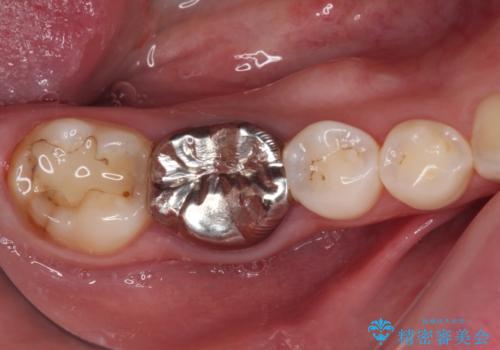

- 奥歯の銀歯が外れたことをきっかけに、全ての銀歯をセラミックに替えたいとのことで来院された患者様です。

第一大臼歯4本と、メタルインレーが装着されている2歯をセラミッククラウンならびにセラミックインレーにて補綴治療・修復治療を行うこととしました。